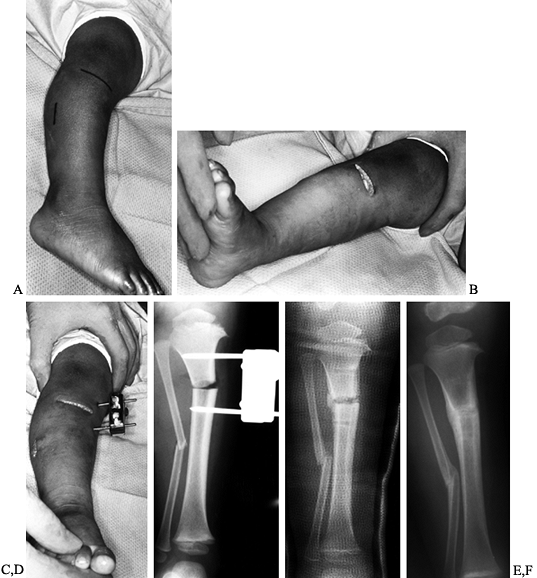

Figure 169.8. A:

Standing preoperative photograph of a 13-year-old African-American boy with bilateral adolescent or late-onset tibia vara. A previous proximal tibial osteotomy was performed on the right, producing only partial correction. Observe the marked obesity and the untreated left genu varum deformity and its medial tibial torsion. The patient subsequently underwent a laterally based closing-wedge proximal tibial osteotomy, including the physis, and a diaphyseal fibular osteotomy for correction of this deformity. B: On a standing AP radiograph of the left knee, the radiographic changes in adolescent tibia vara are less striking than in the infantile form. There is narrowing of the medial aspect of the proximal tibial epiphysis, physeal irregularity, and increased height of the lateral aspect of the epiphysis. |